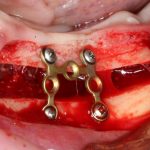

При горизонтальной остеотомии, на мой взгляд, удобнее использовать минипластины. Как я уже отмечал выше, в практике мы используем X- и H-образные минипластины под винты размером 0.9х4мм. Количество металла в разных условиях может быть разным — всё зависит от того, на каком этапе достигается полная неподвижность перемещенного костного фрагмента.